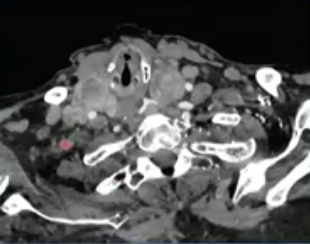

Thyroid artery embolization for Goiter reduction,TAEGR 甲状腺肿大减容动脉栓塞

甲状腺肿大

病因:不是癌症,但5%会含有甲状腺癌(PMID 31542786)